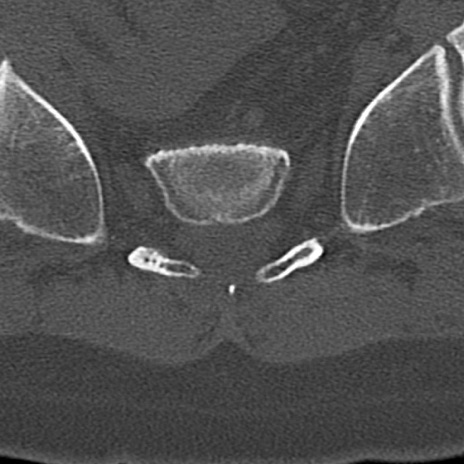

【整形】TIPS症例4 腰椎CT(横断像)

腰椎CT

横断像と矢状断像